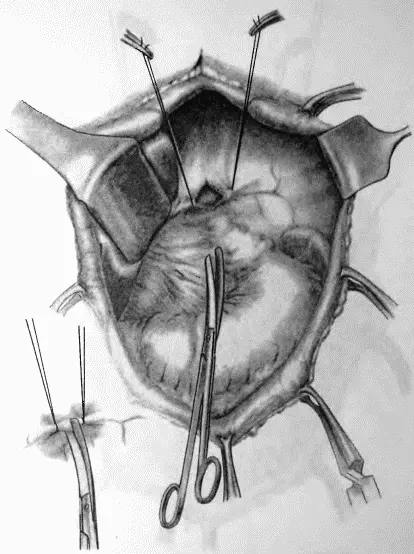

Рис. 76.Сагитальная диафрагмотомия. Анестезия и пересечение левого блуждающего нерва

Рис. 77.Сагитальная диафрагмотомия. Пересечение левого блуждающего нерва

Рис. 78.Рассечение серозного покрова тонкой кишки, указывающего место наложения швов-держалок, и наложение первого шва на тощую кишку и пищевод